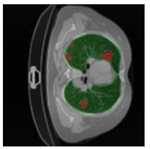

In Table 6, a comparison of the ground truth and prediction results of each model is presented in 2D, along with the 3D projection of each model. The visual analysis of the predictions provides additional insights into the performance of each model. The visualizations demonstrate that Attention UNet captures the intricate details of the lung construction more accurately, resulting in more precise segmentation of the infected areas compared to other models.

Table 6.

Comparison of ground truth and model prediction results using UNet, LinkNet, Attention UNet, UNet 3+, and TransUNet.